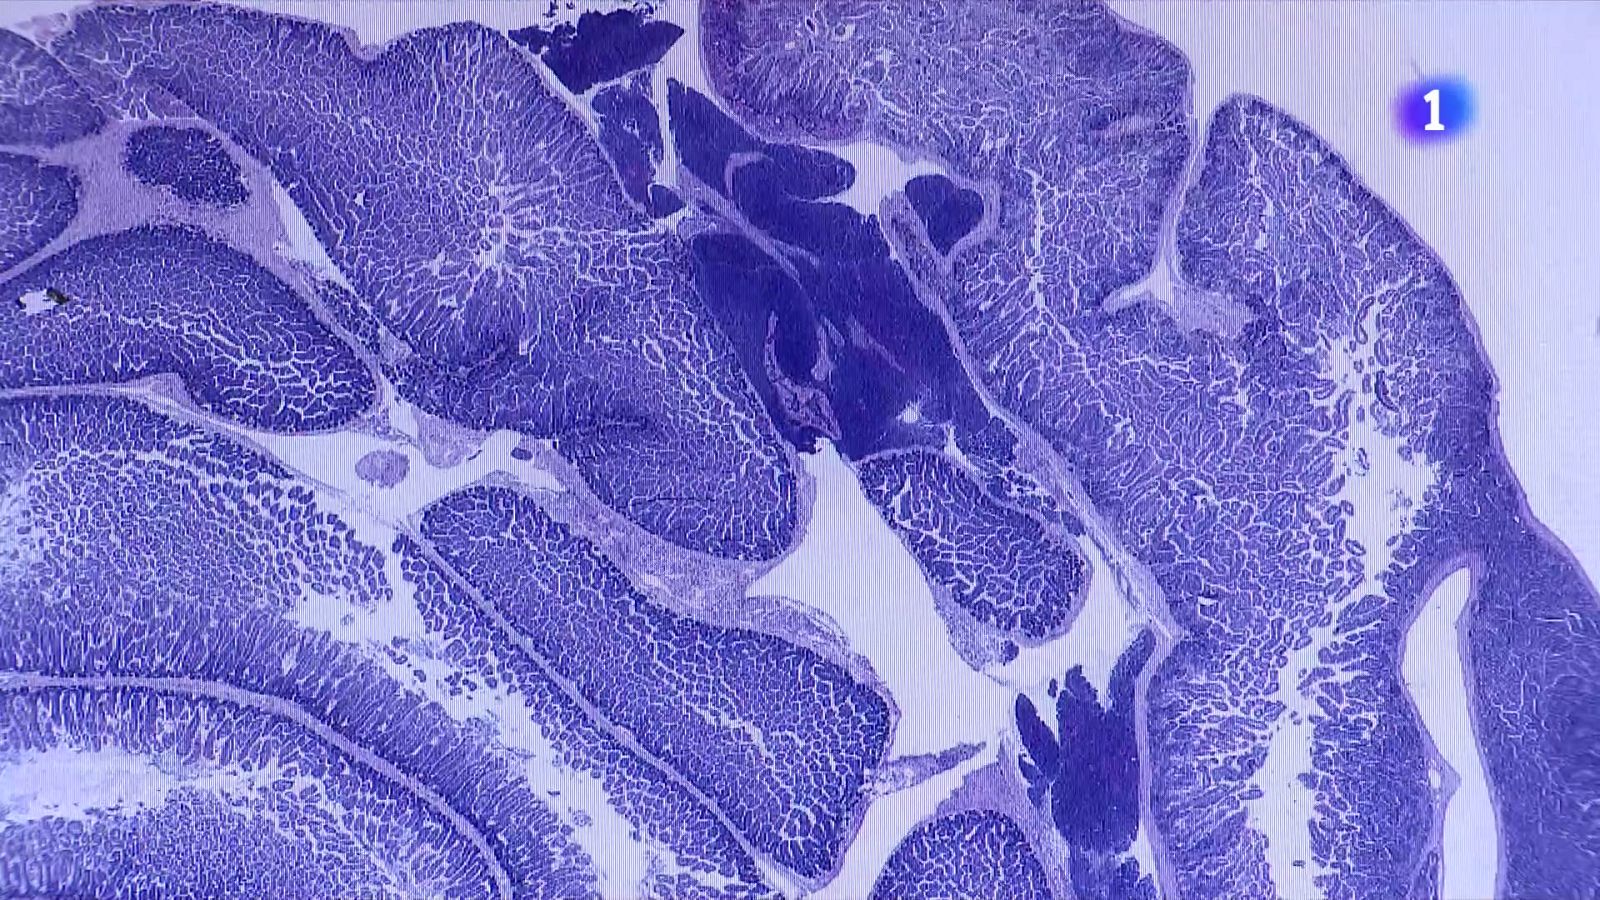

L’Hospital Universitari Vall d’Hebron ha creat la primera Unitat d’Alteració en la Biologia dels Telòmers de l’Adult a Espanya, amb l’objectiu de detectar mutacions genètiques que provoquen un escurçament anòmal dels telòmers. Aquestes estructures, que protegeixen els extrems dels cromosomes, poden escurçar-se prematurament i desencadenar malalties com la fibrosi pulmonar, patologies hepàtiques o neoplàsies hematopoètiques.